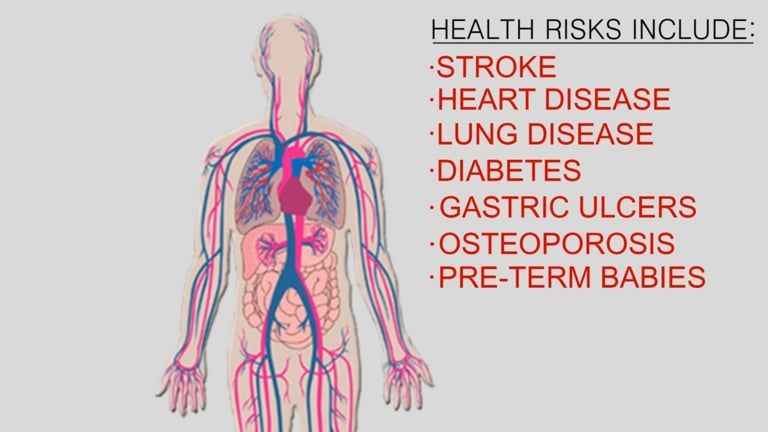

Studies have shown links between periodontal (gum) disease, heart disease and other health conditions.

Research further suggests that gum disease may be a more serious risk for heart disease, more so than hypertension, smoking, cholesterol, gender or age.

Researcher's conclusions suggest that bacteria present in infected gums can become loose and move throughout the body through the bloodstream. Once bacteria reaches the arteries, they can irritate them in the same way that they irritate gum tissue causing arterial plaque, which can cause hardening and affect blood-flow.